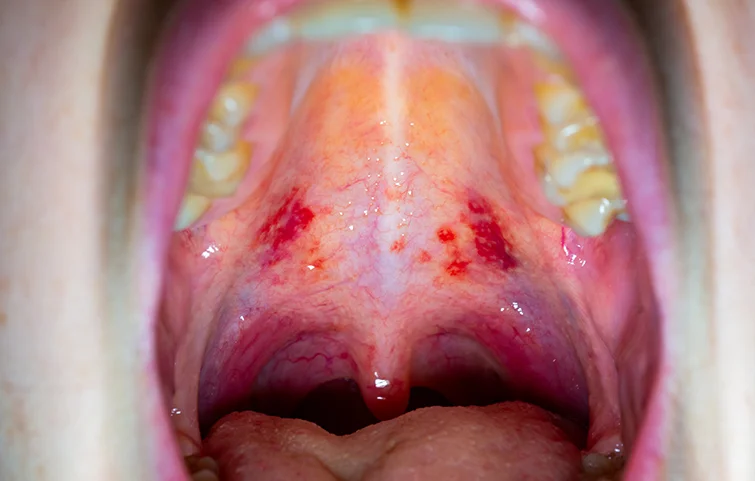

Mouth cancer, also known as oral cancer, refers to cancer that develops in the tissues of the mouth, including the lips, gums, tongue, inner lining of the cheeks, roof and floor of the mouth, and the tonsils. It can occur as a single tumor or multiple lesions and is classified under head and neck cancers.

• White or red patches in the mouth